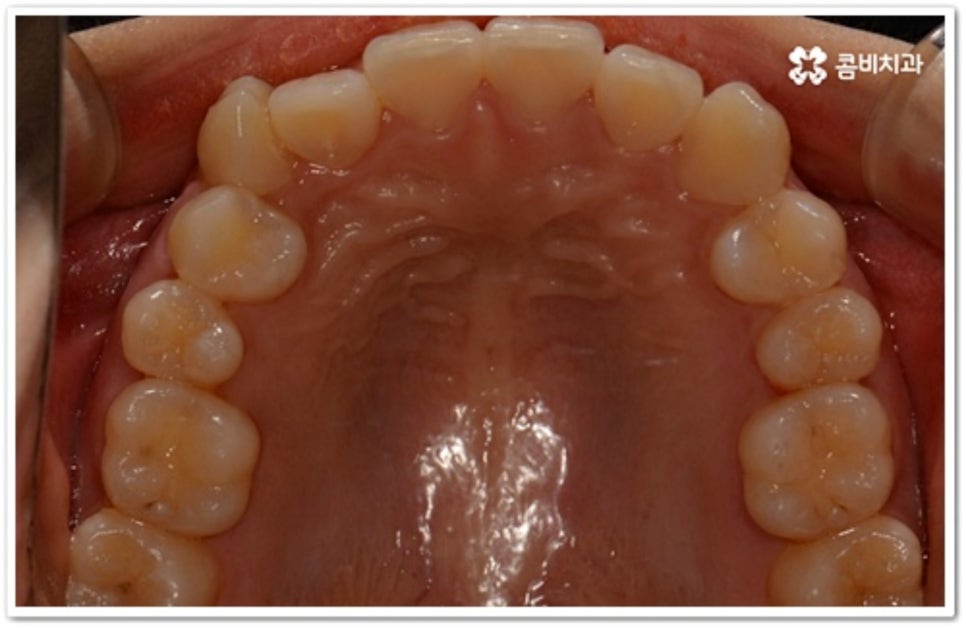

치아는 제자리로 돌아가려는 성질을 가지고 있어서 덧니 발치 교정이 끝난 후 일정 기간 동안은 유지 장치를 착용하여 이를 예방하고 정기 검진을 꼬박꼬박 받으면서 사후 관리를 철저하게 해 주는 게 좋을 거예요. 유지장치에는 고정식과 가철식이 있는데 치아 안쪽에 얇은 철사를 붙이는 고정식 (사진에서 볼 수 있는 사례) 은 앞니가 틀어지는 것을 방지해 주고, 뺐다 꼈다 하는 가철식은 교정 치료할 때 악궁 확장을 한 경우 전체 치열을 유지하기 위해 필요한 방식이라고 할 수 있어요. 환자분들 각각의 치료 과정이나 구강 상태에 따라 둘 중 하나를 선택하거나 두 가지 다 해야 하는 경우가 생길 수 있습니다.